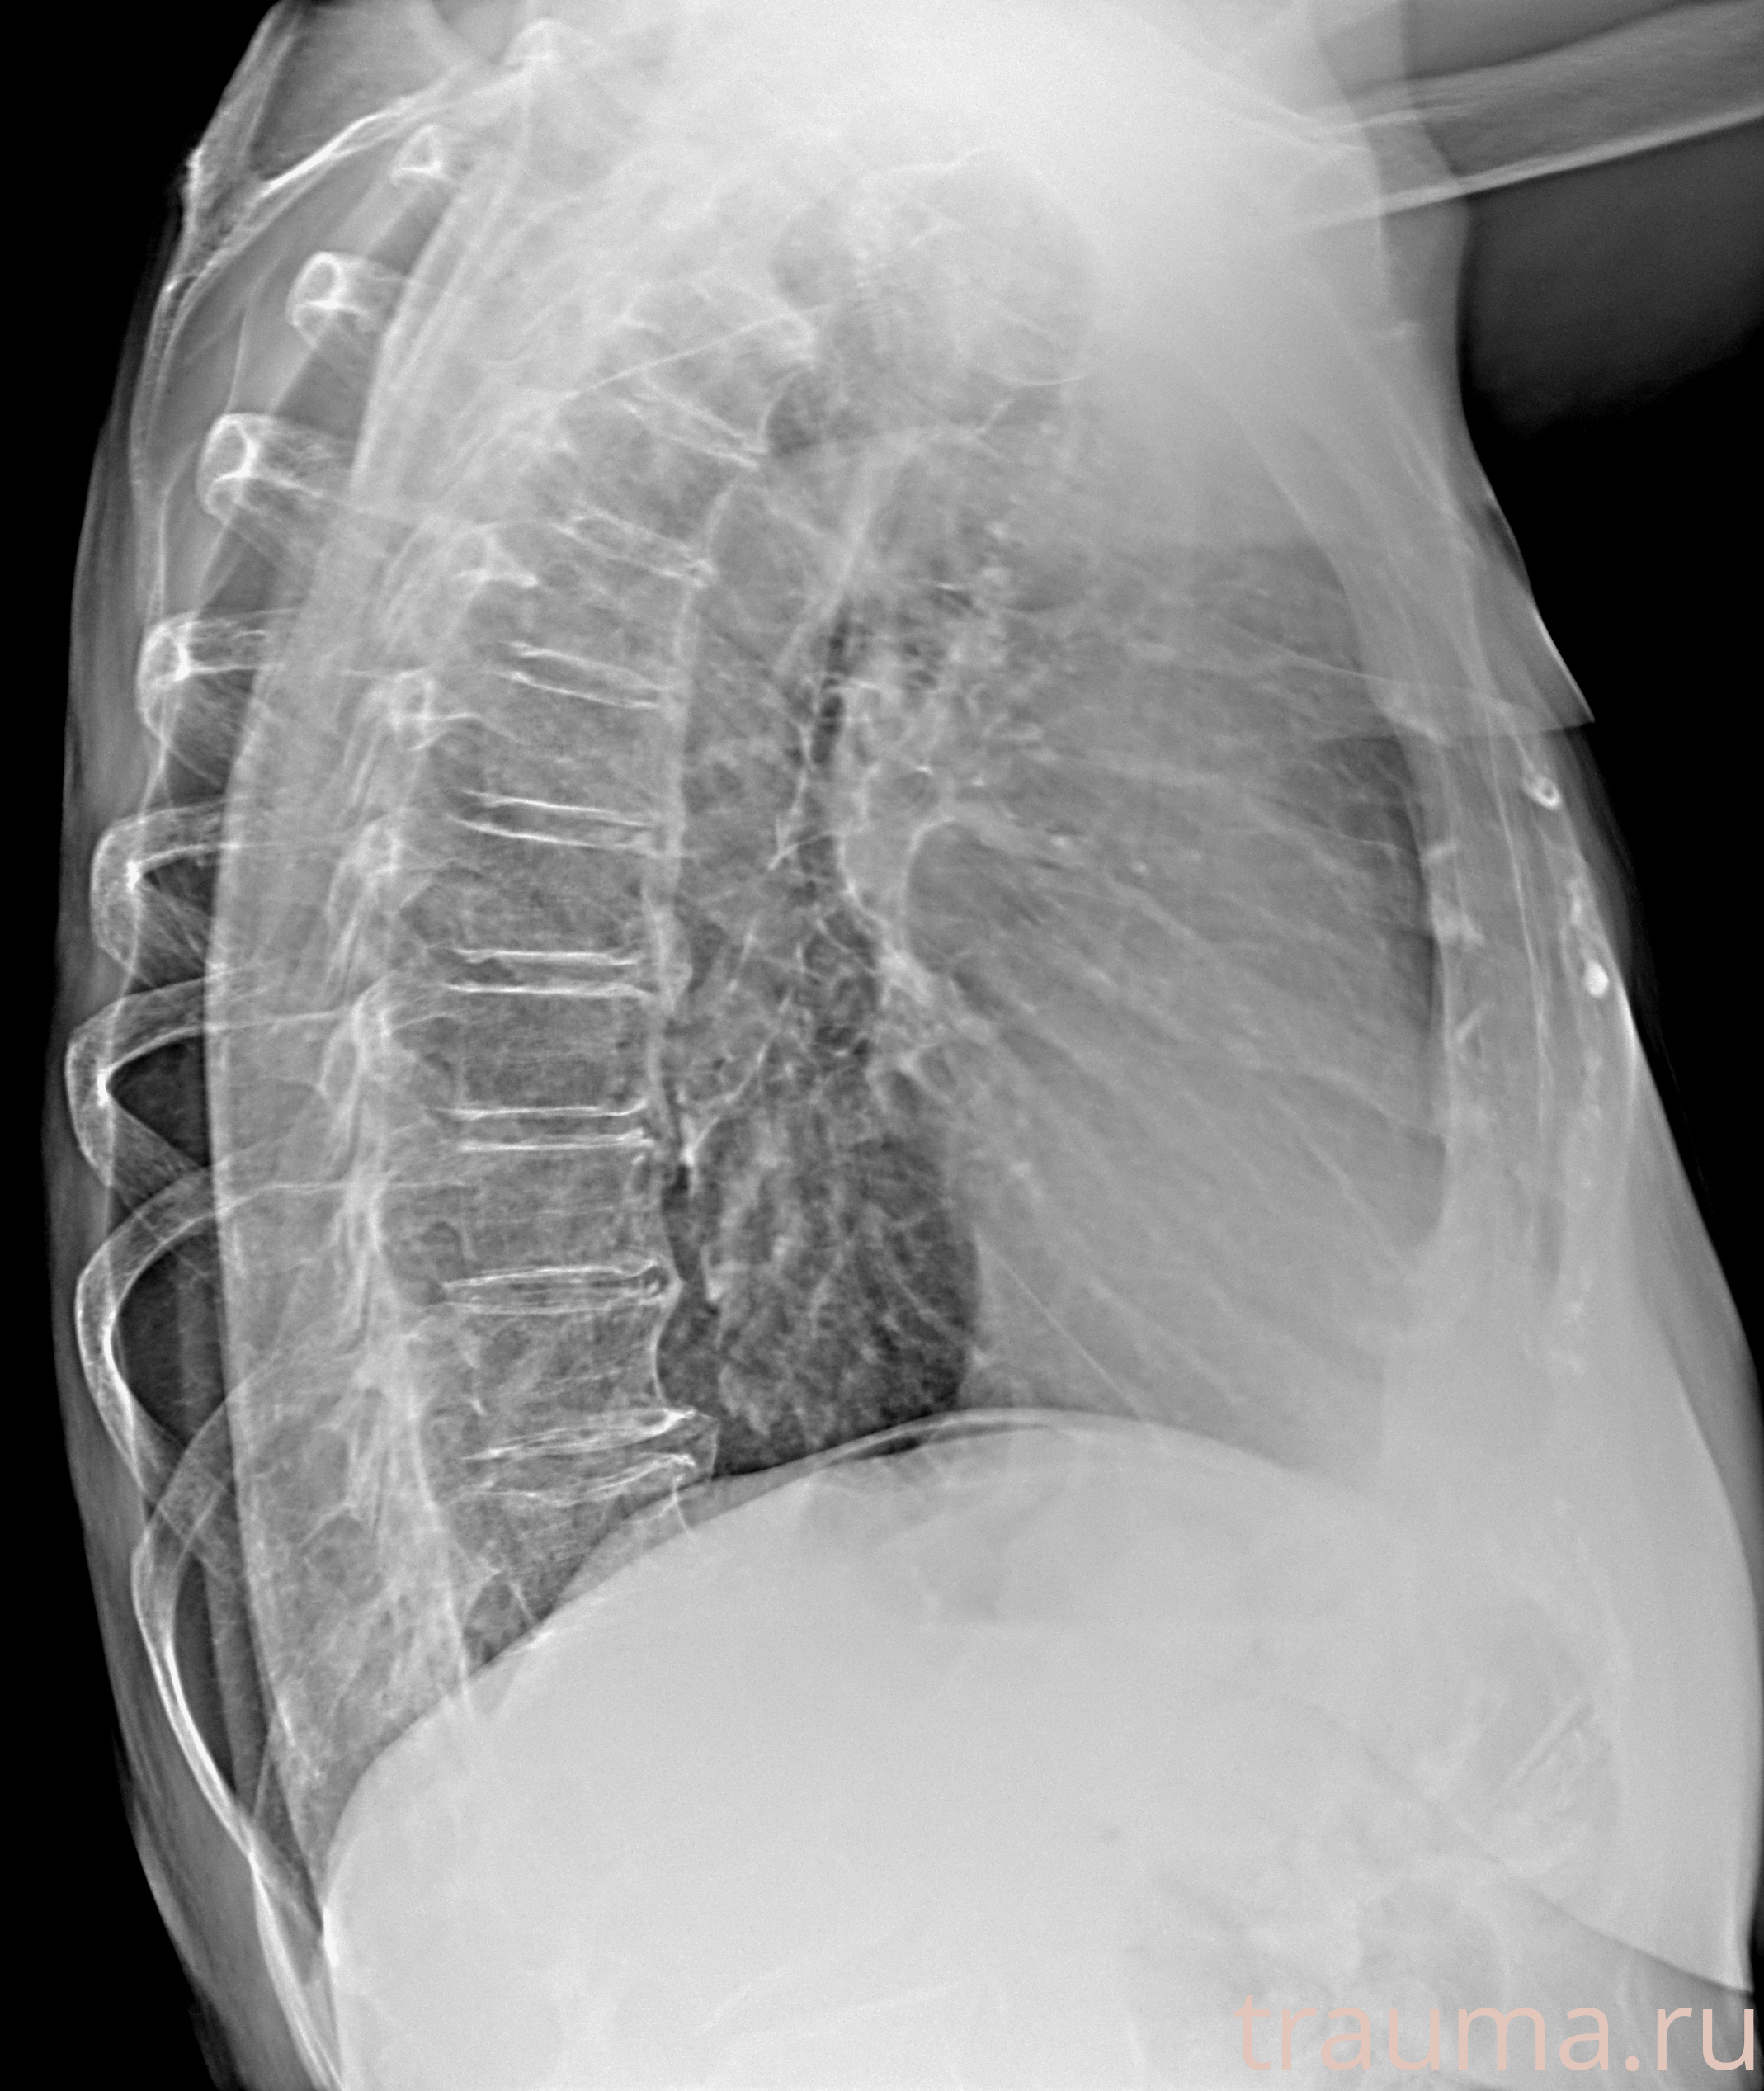

Рентген на дому: по вашему адресу приезжает врач-рентгенолог, травматолог-ортопед с мобильным рентгеновским аппаратом, проводит диагностику травмы или заболевания, делает необходимые рентгенограммы, дает рекомендации по дальнейшему лечению. Получить качественные снимки в домашних условиях возможно благодаря уникальной методике, разработанной МосРентген Центром для института  Склифосовского